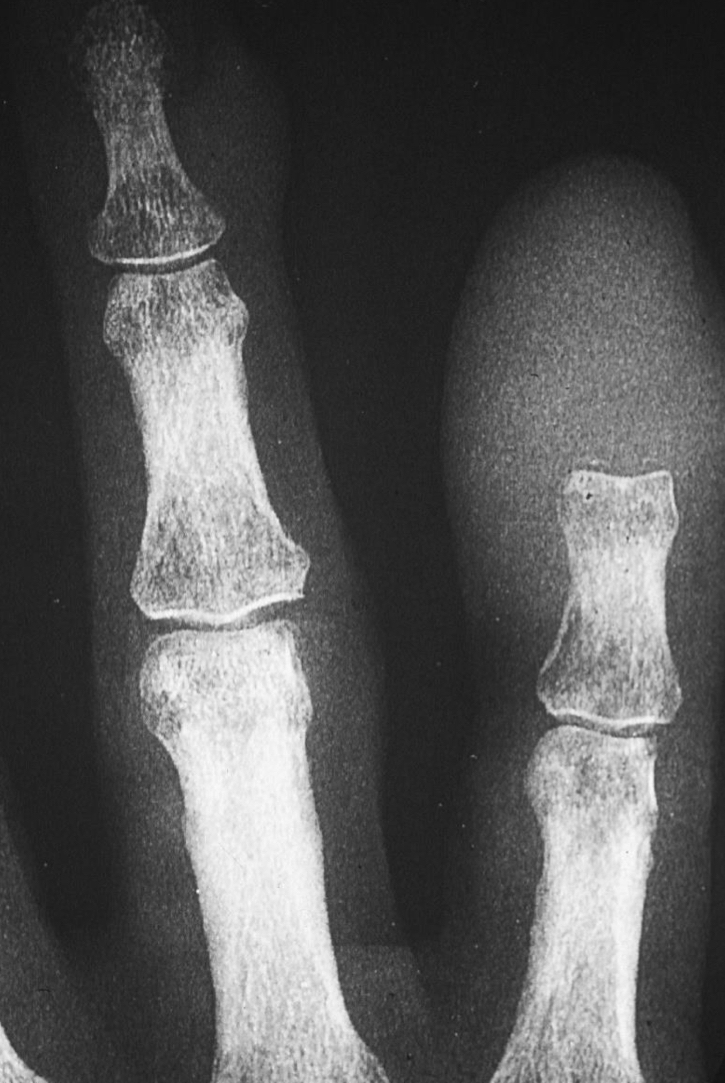

what is this?

acral mets